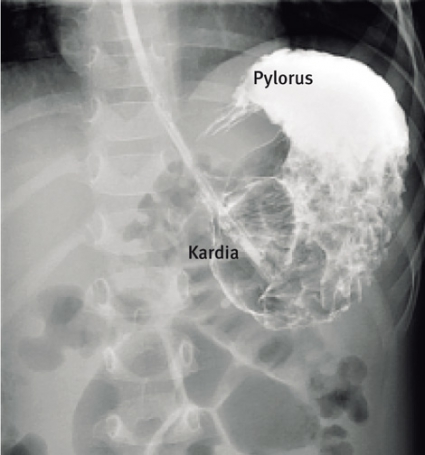

Buköversikt visar en distenderad ventrikel liggande i det vertikala planet (mesenteroaxial) (Figur 2) eller i det horisontella planet (organoaxial) (Figur 3). En kraftigt dilaterad ventrikel kan försvåra diagnosen, eftersom det kan vara svårt att definiera ventrikelns olika delar. Avlastning med ventrikelsond och därefter övre passageröntgen ger diagnosen.

Vid mesenteroaxial volvulus är ventrikeln uppochnervänd, med pylorus ovanför den gastroesofageala övergången (kardia) (Figur 4). Vid organoaxial volvulus är ventrikeln liggande i horisontalplanet, med curvatura major ovanför curvatura minor (Figur 5).